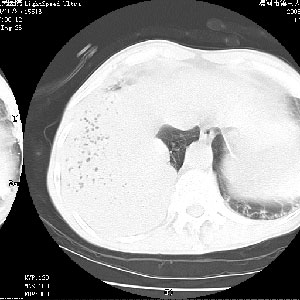

m 老年 发烧、呼吸困难,慢支、肺气肿多年;记的那次是下午大概17:38做的,晚上窒息死亡。

上面的层面就慢性支气管炎肺气肿、肺大泡,别的没有什么、也就不传了。

当时我怀疑:1、阻塞性肺不张早期 2、肺脓肿早期,望老师们发表意见

应该是脓胸的表现,右下肺气管阻塞考虑为痰栓.

你怀疑的有道理,慢支、肺气肿、肺打泡是有了,右下肺的病变有待商议;

首先考虑右下肺炎症并不张,不除外早期肺泡癌改变

病灶边缘清---多个含气小腔---近端未见通畅气管影-----支持-----慢性肺脓肿继发阻塞性肺不张

阻塞性肺不张原因-----脓液未排出

1、右侧脓胸;2、copd;

3、细支气管肺泡癌可以排除,病变以斜裂为界,呈大片状高密度影,内可见多发小气泡,表明有产气杆菌感染所致,内无明显的支气管“枯树枝征”表现,再结合其临床改变(细支气管肺泡癌临表表现重、影像表现轻)所以不符合细支气管肺泡癌(炎症型)的改变。

病变按肺叶分布,病变内可见多个小空腔影,未见充气支气管影,中间段支气管管腔肺窗示密度欠均匀,下肺支气管分叉处基底段支气管隐约可见,未见明显狭窄,中叶支气管通畅,

考虑:阻塞性肺炎伴小脓肿形成可能性大。(痰栓可能性大)

右下肺实变,内有弥漫分面小气泡而无支气管征,叶间裂前移,呈臌大之形,而无收缩之状,兼纵隔稍左行移,故。不支持不张,倒支持大叶肺叶,如楼上所说,小气泡不象残留之肺,不可以考虑产气菌感染吗。

阻塞性肺炎,肺脓肿形成。依据,右下支气管不通,大片实变形内可见小气泡。不支持肺不张。